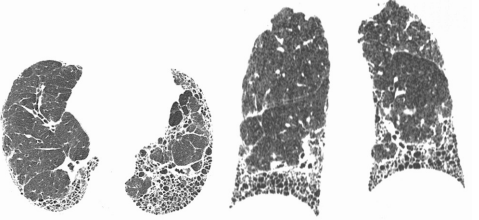

Tomografia de tórax:

LAUDO: padrão típico de pneumonia intersticial usual. Imagens de TC do tórax em janela de pulmão no plano axial mostrando opacidades reticulares, bronquiectasias de tração e extenso faveolamento associado, e imagens em reformatação coronal evidenciando gradiente apicobasal do acometimento.